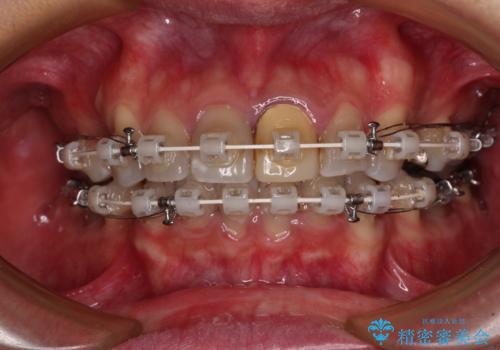

- 矯正装置

- 審美装置

- 飛び出した前歯を気にして来院された患者様です。

口元を引っ込めるために上下左右の第一小臼歯4本を抜歯することとしました。

速やかに治療を進めたいとのことで、表側のワイヤー装置で矯正治療を行うこととしました。